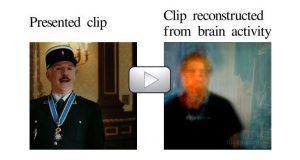

Mixing in a typical fMRI brain scanner with advanced computer modeling simulations, scientists at the University of California have managed to achieve the the unthinkable – render the visual expressions triggered inside the brain and play them like a movie. This is the forefront technology which will one day allow us to tap inside the mind […]